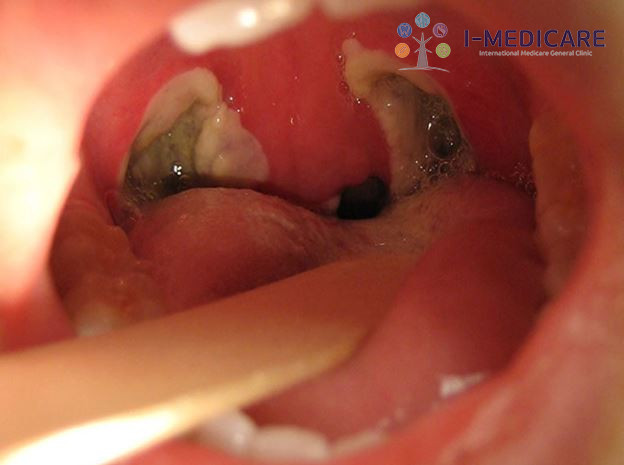

Viêm họng mãn tính đợt cấp là gì? Nhận biết để tránh biến chứng - ảnh 1